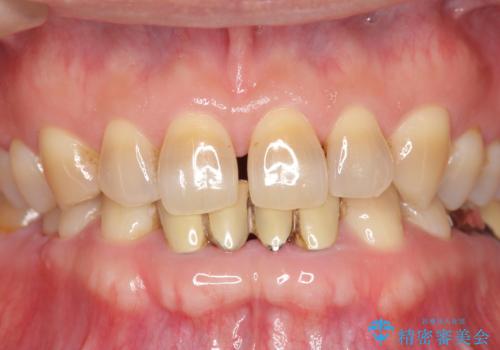

下の前歯のブリッジ 保険治療のやり替え

- 前歯のブリッジのやり替えをご希望されました。

かみ合わせが強く、以前入っていた保険治療のブリッジも前装が欠けてしまっていました。